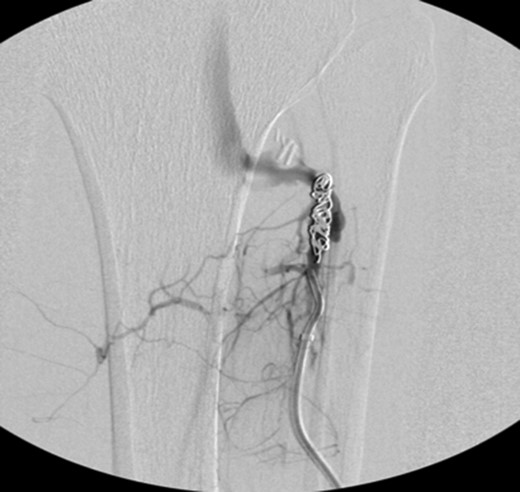

Patient underwent a left lower extremity angiogram. During the procedure she was found to have patent aorta and bilateral common iliac artery. There was no disease visualized in the left external iliac artery, common femoral artery (CFA), SFA, patent previously placed stent, patent above and below the knee PA and two vessel run off to the foot (Fig. 1). Upon delayed fluoroscopic images we identified contrast filling the deep venous system rather quickly suggesting a high volume fistula (Fig. 2). We then identified the fistula between ATA and ATV. Although ATA was previously ligated there was retrograde filling of the artery from unnamed branches, which communicated with the venous system as shown in. In the midcalf (ATA) was cannulated with a micropuncture needle. Micropuncture wire was inserted and a 5-Fr sheath was inserted after exchanging over wire. At this point VortX coils (Boston Scientific) were placed from the curve of ATA until the whole AVF was sealed. Anterograde angiogram showed no flow through the fistula (Figs 3 and 4). There was a palpable PT and DP pulse at the completion of the procedure. Sheath was removed, pressure dressing applied. Patient was discharged home same day. Recovery has been unremarkable. Three months follow-up claudication symptoms have significantly improved.

VortX coils (Boston Scientific) were placed from the curve of anterior tibial artery to its communication with venous system.

Anterograde angiogram showed no flow through the fistula tract with two vessels run off.